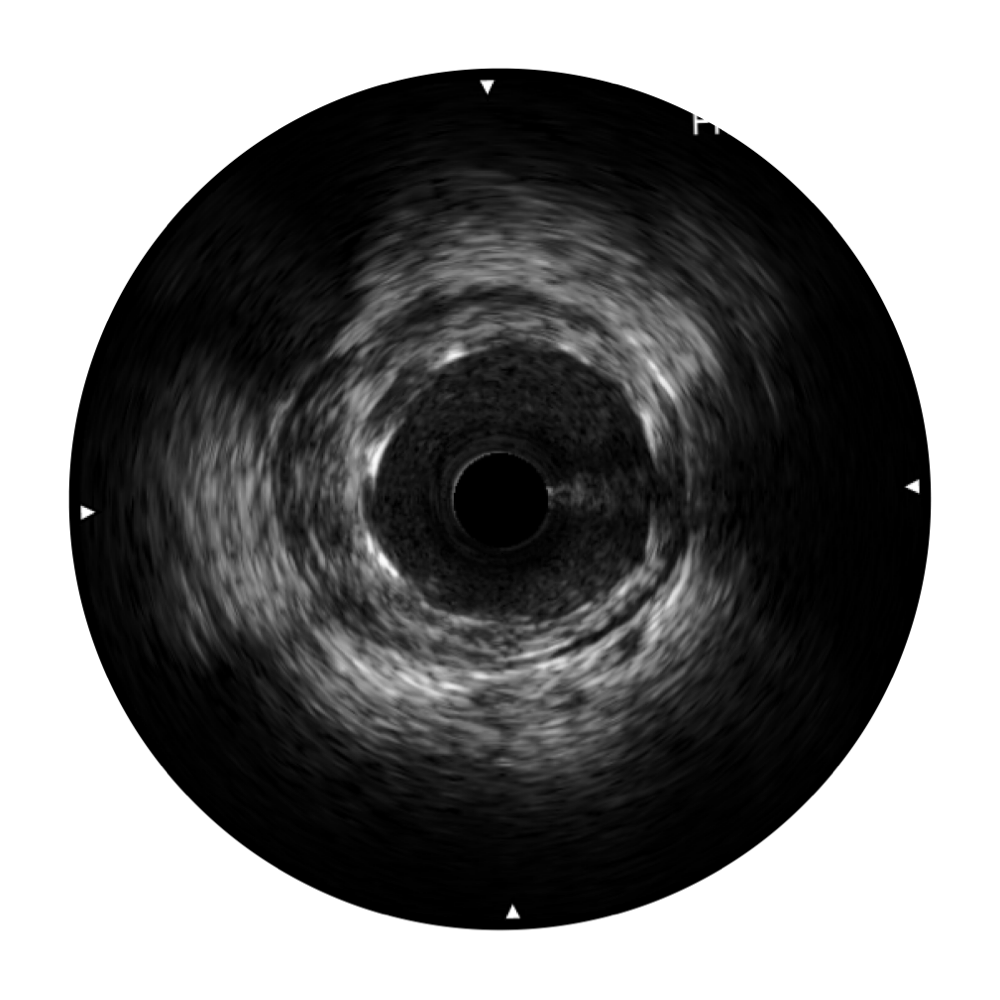

milan米兰宽频IVUS图像

传统IVUS图像

对比传统IVUS导管成像,milan米兰宽频IVUS图像的近场支架梁显影更细腻,远场中膜外血管仍清晰可辨,兼顾远中近,兼顾分辨力与穿透深度